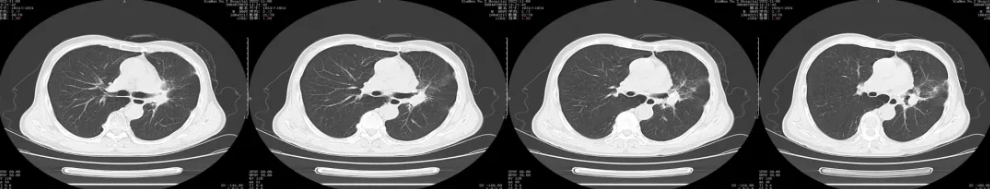

胸部CT平扫+增强:

疗效评价:PR (左肺门病症明显缩小,结构清晰)

后续治疗:2020-06-22日开始给予左肺门进行放射治疗

疗效评价:PR/SD(放疗结束后复查CT未见明显放射性肺炎及不良反应)

后续治疗:放射治疗结束后,继续给予原方案化疗2周期,复查胸部CT,疗效评价PR,病情稳定